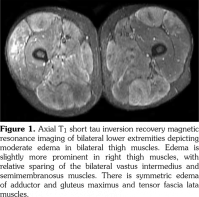

The patient had positive antinuclear antibody, with titer 1:1280 in a speckled immunofluorescence pattern and positive Sjögren’s syndrome antibody. The erythrocyte sedimentation rate was mildly elevated at 35 mm/hour and anti Jo-1 antibody was negative. These findings, along with the physical exam findings of lacrimal and parotid glands enlargement, were consistent with the Sjögren’s syndrome. The magnetic resonance imaging of bilateral thighs showed symmetric muscle edema of the thigh muscles (Figure 1). There was also moderate symmetric edema of the tensor fascia lata and gluteus maximus muscles. Given the symmetric muscle involvement and positive antinuclear antibody markers, rhabdomyolysis was deemed to be related to an inflammatory myopathy associated with Sjögren’s syndrome.